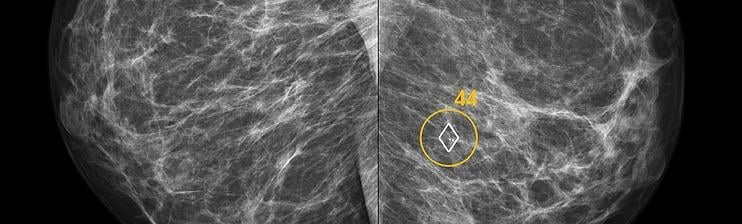

ScreenPoint recently announced it has received 510(k) clearance from the U.S. Food and Drug Administration (FDA) for Transpara detection and decision support software, designed to assist radiologists with the reading of screening mammograms. Transpara is the first AI application for detecting breast cancer in screening mammograms to gain FDA 510(k) clearance, based on its functionality that interactively provides support for detection and diagnosis.

“Compared to traditional mammography computer-aided detection (CAD) products, ScreenPoint’s decision support product Transpara delivers much more clinically useful information to the radiologist,” said Ritse Mann, M.D., Ph.D., breast imaging specialist at Radboud University Medical Center, Nijmegen, Netherlands, who uses the system clinically and evaluated its performance in several studies, “I can use Transpara as a second reader and its opinion is as good as when I would ask a colleague.”